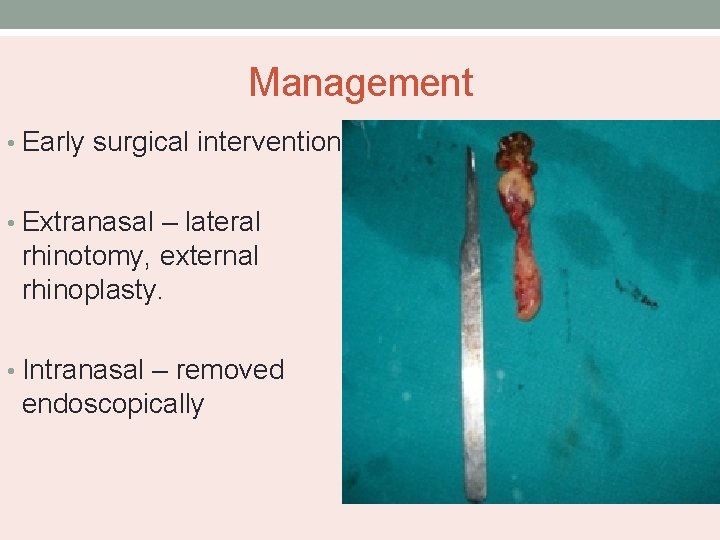

Management • Early surgical intervention • Extranasal – lateral rhinotomy, external rhinoplasty. • Intranasal – removed endoscopically